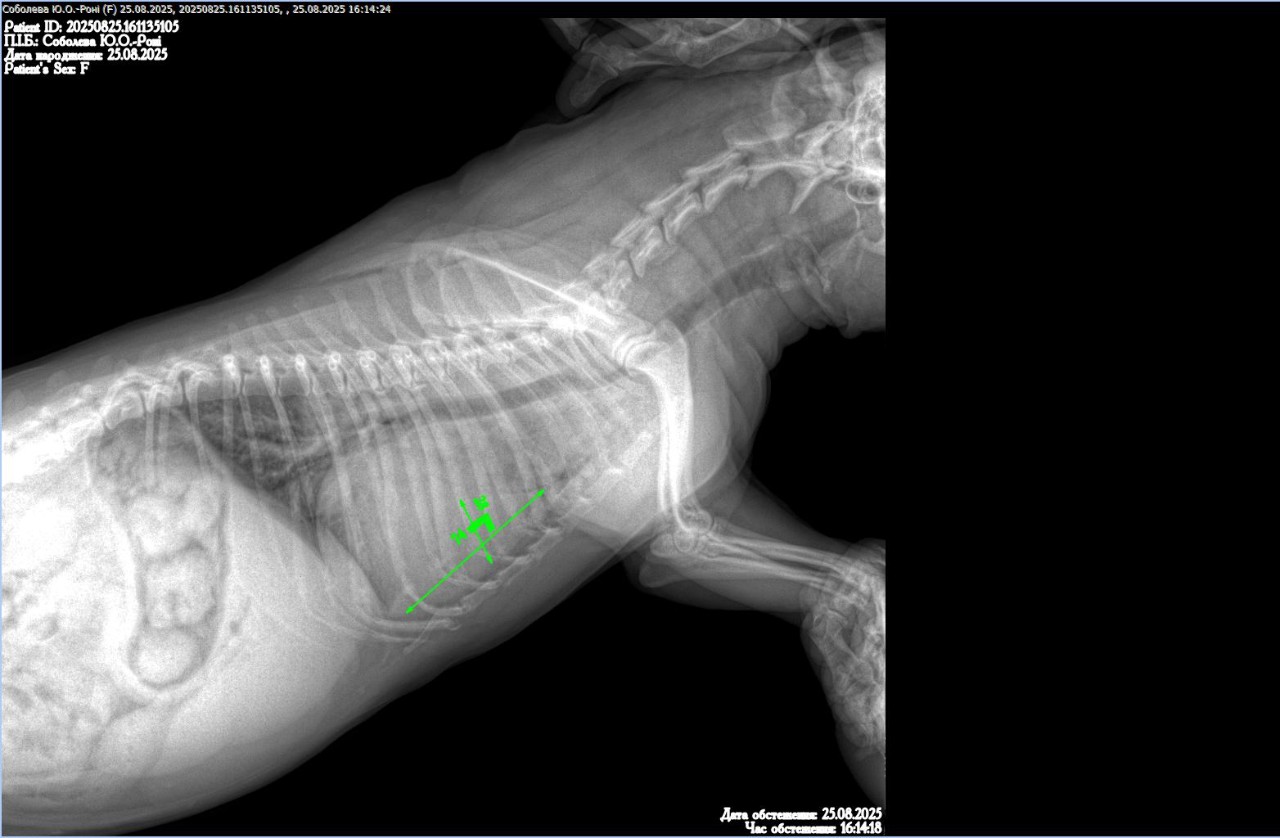

Добрый день уа. Врачи у меня неординая просьба к вам, так как мы находимся прифронтовой зоне и сейчас нет возможности выехать мы не можем помочь своему четверолапому. У него кашель, сердце исключили, сказали искать проблему в легких, рентген нам получилось сделать, а вот описание ренгена нет, ветгруппы нам не помогли. Если это возможно, помогите нам пожалуйста! Очень просим помощи, спасибо.